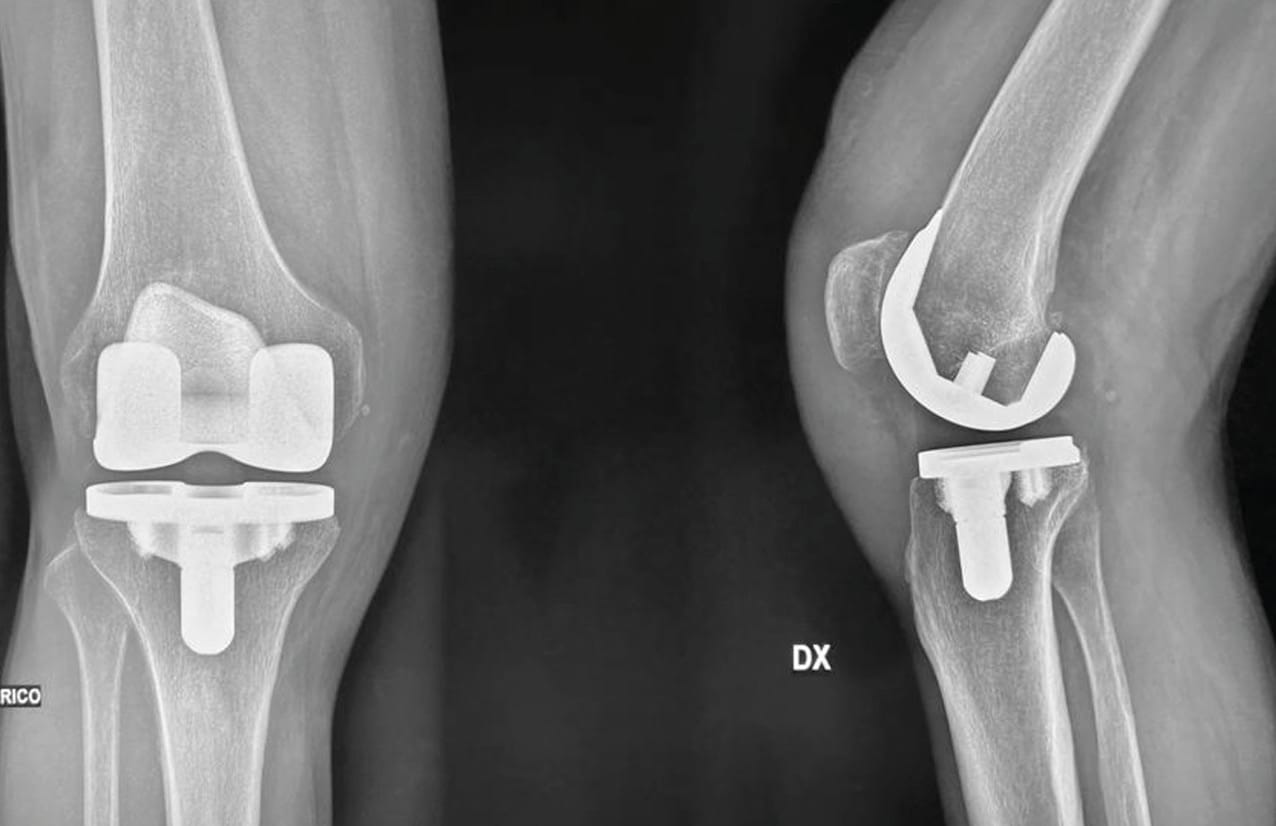

Cementless fixation in young or obese patients

Cementless components represent a significant evolution in modern TKA practice, supported by evidence demonstrating superior performance particularly in specific patient populations alongside advancing implant technologies. Registry data revealed consistent annual increases in cementless utilization, achieving 22% adoption in 2023 with continued growth projected as clinical evidence expands [40] American Academy of Orthopaedic Surgeons (AAOS). American Joint Replacement Registry (AJRR): 2024 Annual Report. Rosemont, IL: 2024.. This trend reflects the increasing recognition that cemented fixation may be inadequate for high-demand demographics, particularly young, active patients, males, and obese individuals where mechanical stresses may surpass cement-bone interface durability.

Registry analyses demonstrated higher aseptic loosening rates in males under 65 years with cemented implants compared to cementless ones, while patients with BMI exceeding 35-40 exhibited higher failure rates cemented implants compared to cementless alternatives [40], American Academy of Orthopaedic Surgeons (AAOS). American Joint Replacement Registry (AJRR): 2024 Annual Report. Rosemont, IL: 2024.[41] Australian Orthopaedic Association National Joint Replacement Registry (AOANJRR). Hip, knee and shoulder arthroplasty: 2024 Annual Report. Adelaide: Australian Orthopaedic Association; n.d.. Enhanced cementless prosthetic performance has been enabled by advanced implant designs featuring the four-peg-one-keel configuration that establishes reliable primary stability, addressing historical concerns regarding initial fixation adequacy [42] Wang K, Sun H, Zhang K, Li S, Wu G, Zhou J, et al. Better outcomes are associated with cementless fixation in primary total knee arthroplasty in young patients: A systematic review and meta-analysis of randomized controlled trials. Medicine (Baltimore) 2020;99:e18750. https://doi.org/10.1097/MD.0000000000018750..

Meta-analyses in younger patient cohorts revealed multiple advantages favouring cementless over cemented fixation, including superior patient-reported outcome measures, reduced pain scores, improved range of motion, and decreased component radiolucency rates [42], Wang K, Sun H, Zhang K, Li S, Wu G, Zhou J, et al. Better outcomes are associated with cementless fixation in primary total knee arthroplasty in young patients: A systematic review and meta-analysis of randomized controlled trials. Medicine (Baltimore) 2020;99:e18750. https://doi.org/10.1097/MD.0000000000018750.[43] Chen C, Li R. Cementless versus cemented total knee arthroplasty in young patients: a meta-analysis of randomized controlled trials. J Orthop Surg Res 2019;14:262. https://doi.org/10.1186/s13018-019-1293-8.. In high-BMI populations, the evidence proved particularly compelling, with cementless implants demonstrating aseptic loosening rates of only 0.9% compared to 18.8% in cemented groups, yielding survivorship rates of 99.1% versus 88.2% at eight-year follow-up [44] Sinicrope BJ, Feher AW, Bhimani SJ, Smith LS, Harwin SF, Yakkanti MR, et al. Increased Survivorship of Cementless versus Cemented TKA in the Morbidly Obese. A Minimum 5-Year Follow-Up. J Arthroplasty 2019;34:309–14. https://doi.org/10.1016/j.arth.2018.10.016..

Pooled analyses indicated substantial benefits of cementless implants among high BMI patients, with odds ratios of 0.17 for all-cause revisions and 0.15 for aseptic loosening, representing considerable risk reductions that support expanding cementless fixation adoption [45] Goh GS, Fillingham YA, Sutton RM, Small I, Courtney PM, Hozack WJ. Cemented Versus Cementless Total Knee Arthroplasty in Obese Patients With Body Mass Index ≥35 kg/m2: A Contemporary Analysis of 812 Patients. The Journal of Arthroplasty 2022;37:688-693.e1. https://doi.org/10.1016/j.arth.2021.12.038..